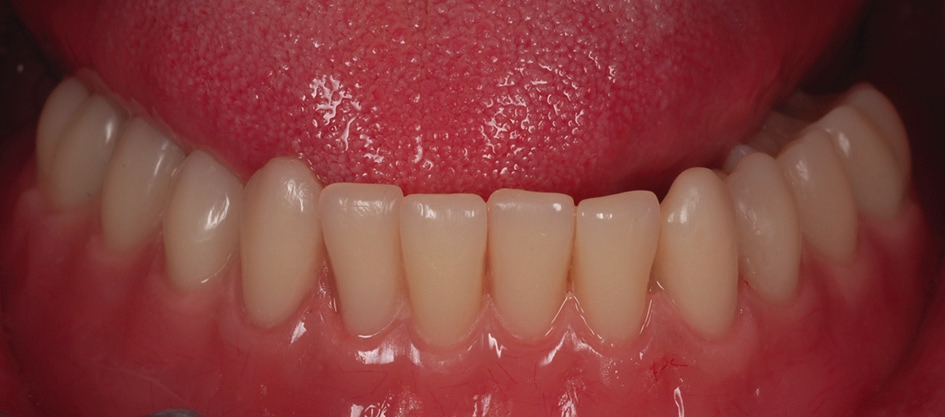

Als dritte Behandlungsoption wurde eine bedingt herausnehmbare Rekonstruktion gewählt, die auf den systemeigenen PS MultiPlus-Abutments befestigt wurde (Abb. 16 und 17). Grundlage für die bedingt herausnehmbare Brücke war ein mittels Selective Laser Melting hergestelltes Kobalt-Chrom Gerüst (EOS; Electro Optical Systems München, Deutschland). In unserem Patientenfall konnte eine sehr gute, passgenaue Herstellung des Metallgerüsts erfolgen (Abb. 18). Das Gerüst wurde mittels Komposit (anaxblend big block dentin und big block enamel, anaxdent GmbH, Stuttgart, Deutschland) verblendet (Abb. 19a und b). Die Schraubenkanäle wurden nach Einsetzen der Suprakonstruktion mit Komposite (EcuSphere-Carat, DMG Chemisch- Pharmazeutische Fabrik GmbH, Hamburg, Deutschland) verschlossen (Abb. 20). Das klinische Endergebnis war für den Patienten sehr zufriedenstellend, da die Rekonstruktion sehr natürlich und ästhetisch gestaltet war (Abb. 21).